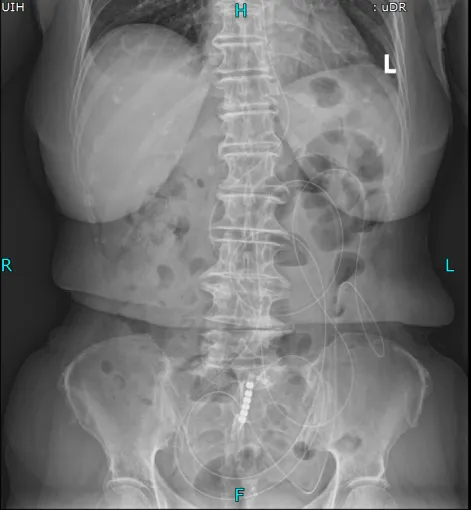

from clipboard术前立位腹平片

主任医师叶晋生结合病历和CT检查结果,明确诊断:低位小肠梗阻,且王奶奶有两次腹部手术史,肠粘连概率极高,肠管随时可能因过度扩张穿孔,需要先减压再评估。